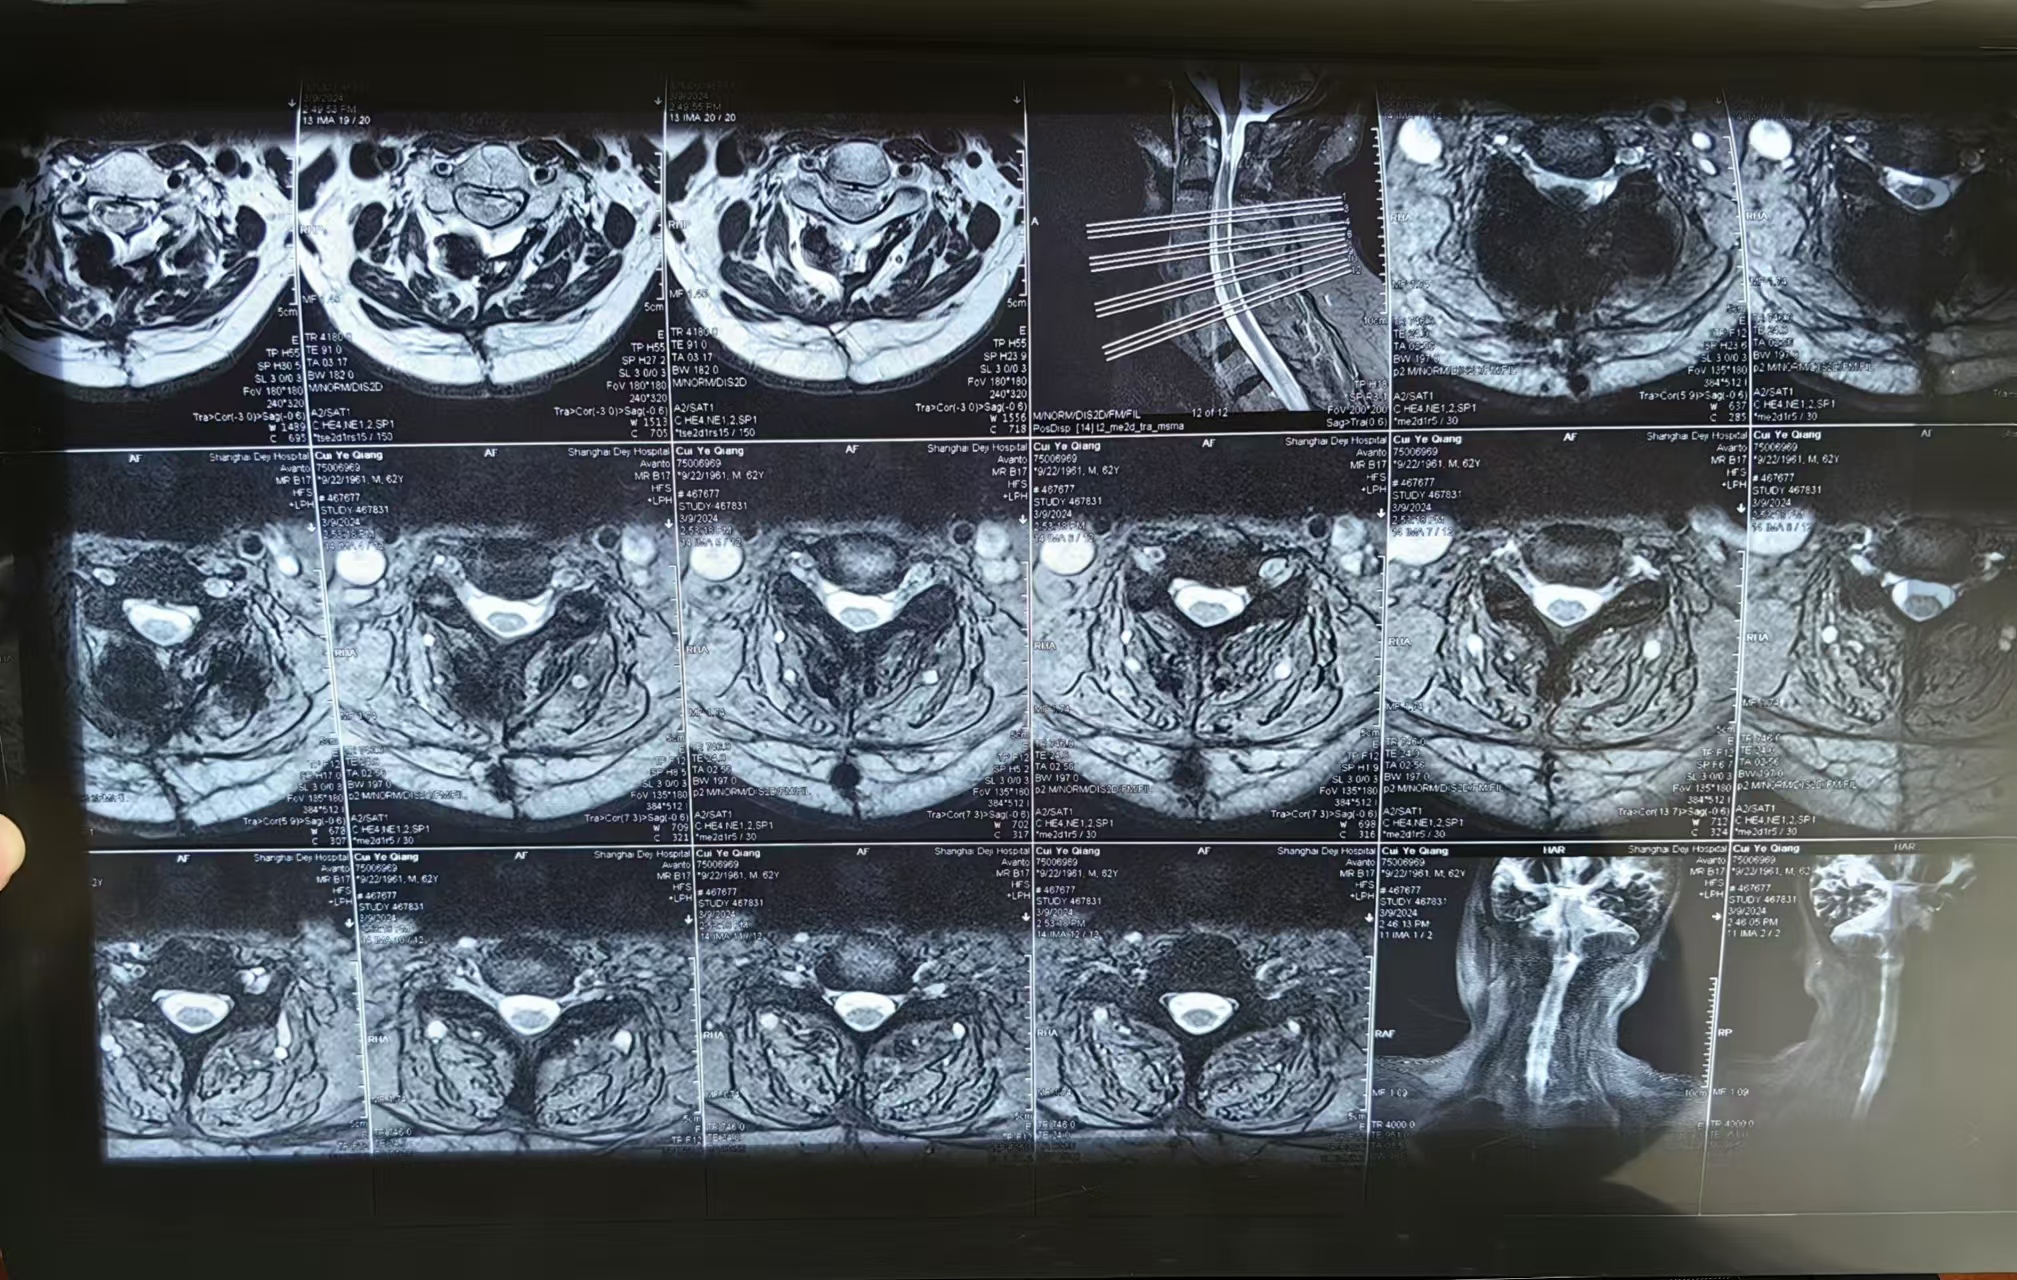

• 2023.09.01,复查,压迫脊髓。

• 术后影像:

• 2024.03.09,复查,对位良好,但术前症状难以恢复。